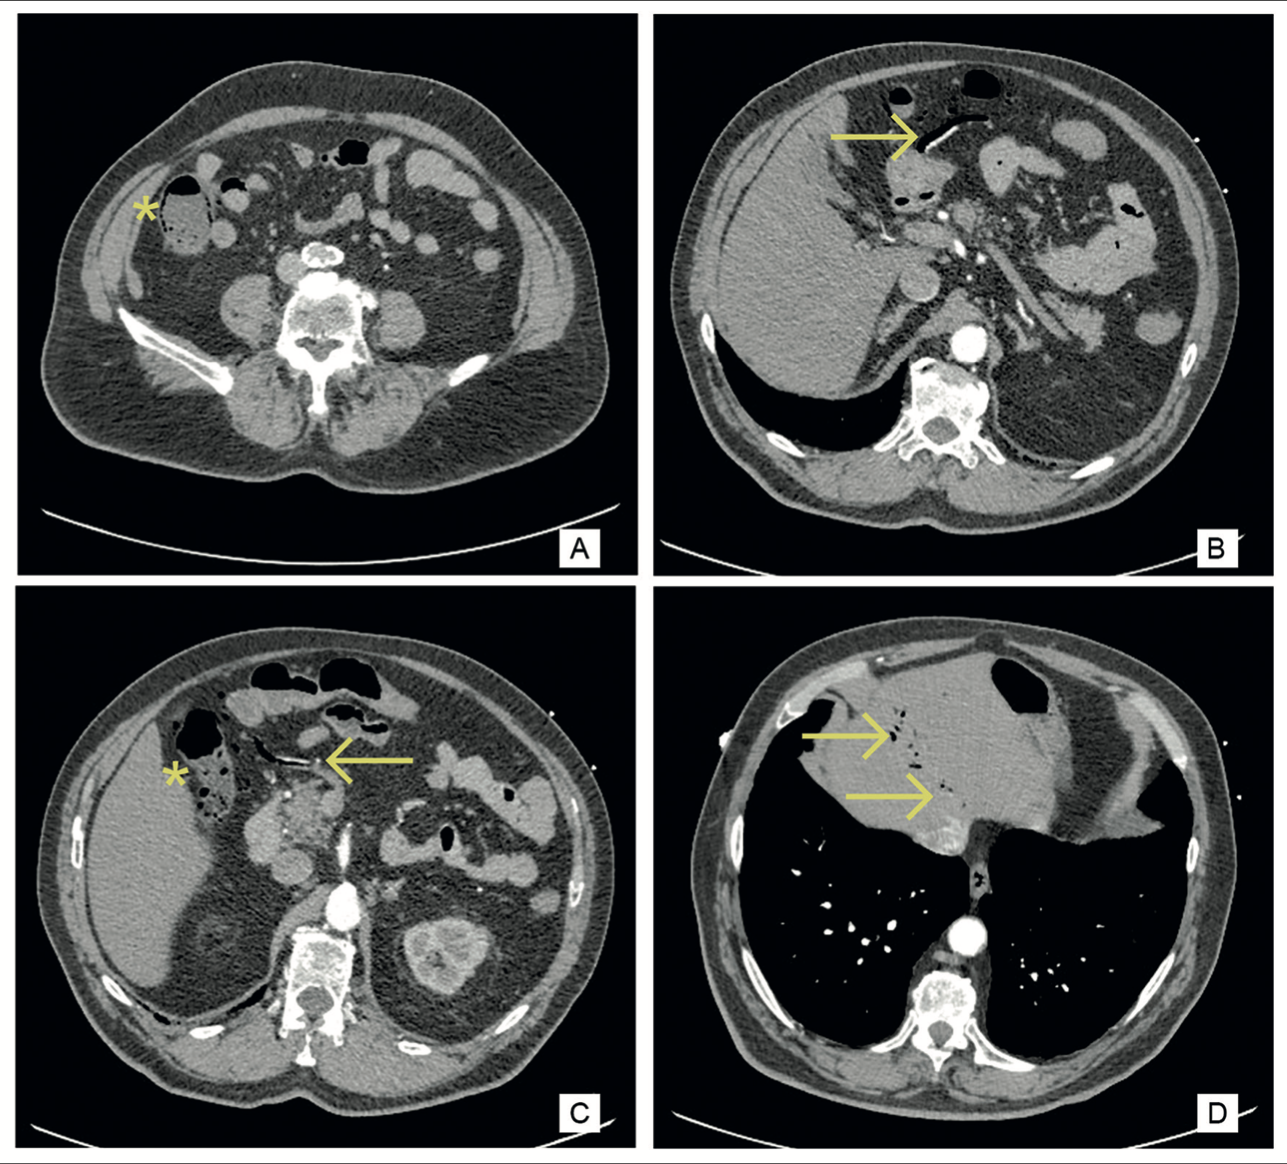

Imágenes y Cirugía

Caterina Contreras Bertolo, Javier Vela Ulloa, Felipe Bellolio Roth